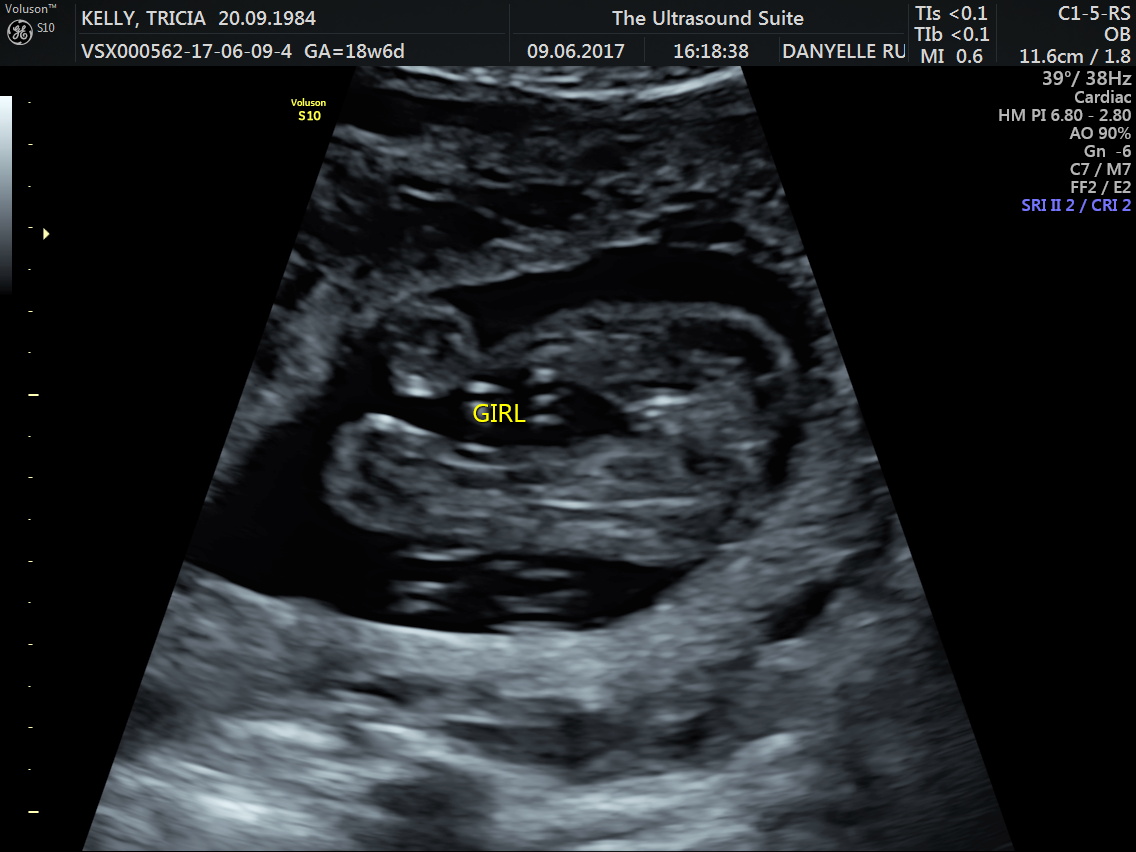

Just like title suggests Im finding it hard to believe i could possibly be getting my longed for little girl. This pic is 19 weeksAttachment 36572